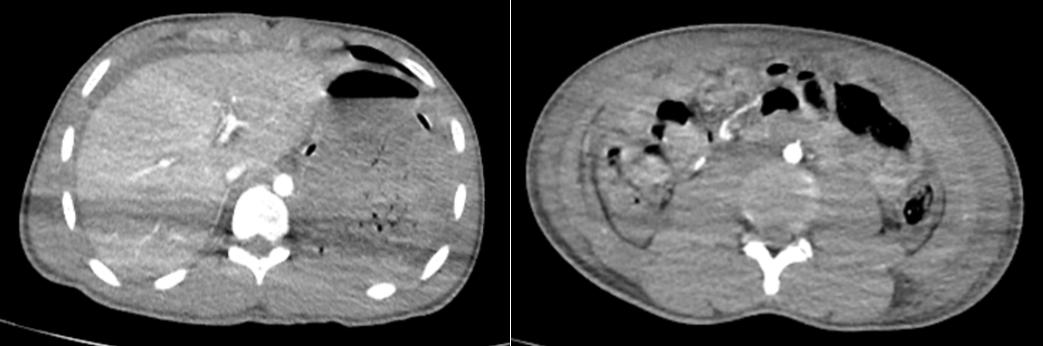

Ngày 12/01 bệnh nhân đau bụng dữ dội, bụng phản ứng, chụp chụp cắt lớp vi tính có hơi tự do ổ phúc mạc.

Hình ảnh hơi tự do ổ phúc mạc vào ngày thứ 12 sau nhập viện trên phim chụp cắt lớp vi tính

Bệnh nhân được chỉ định mổ cấp cứu, kết quả trong mổ hoại tử thủng đoạn cuối hồi tràng cách góc hồi manh tràng khoảng 20cm, kích thước lổ thủng khoảng 0,5cm, thành ruột xung quanh phù nề, có máu tụ quanh lỗ thủng, không có ổ tụ dịch tiêu hóa hay áp xe cạnh chỗ thủng, mạc treo ruột non không tổn thương. Bệnh nhân được cắt bỏ hình chêm phần ruột thương tổn, khâu phục hồi ruột 2 lớp mũi rời bằng chỉ Vicryl 3.0, rửa bụng, dẫn lưu douglas. Hậu phẫu bệnh ổn.